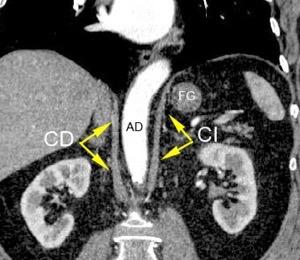

“Seudoquiste pancreático”

5. Otras lesiones

Seudoquiste pancreático

3 rasgos:

1. Conexión entre mediastino y lesión pancreática.

2. Derrame pleural

Matsusue E et al.Three cases of mediastinal pancreatic pseudocysts. Acta Radiol Open. 2016 .

3. Hallazgos de pancreatitis. Panda A et al. “Straddling Across Boundaries”. Thoracoabdominal Lesions: Spectrum and Pattern Approach.Curr Probl Diagn Radiol, 2015